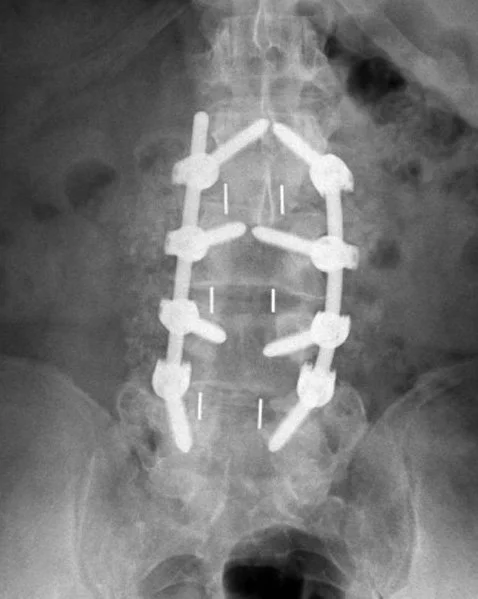

Below is a Video Testimonial from a client from Sandhurst who had been suffering with lower back pain for nearly 20 years. After trying many therapies over the years, she ended up having Lumbar Fusion Surgery 3 years ago.

After the invasive operation she was still in pain, but luckily sought help from One | Body…

Post Lumbar Fusions are one of the most difficult presentations to help as the Scars and Hardware cause nervous system & receptor chaos! That’s in addition to the original underlying cause, which the surgery doesn’t remotely address. Spinal fusions are usually best avoided!